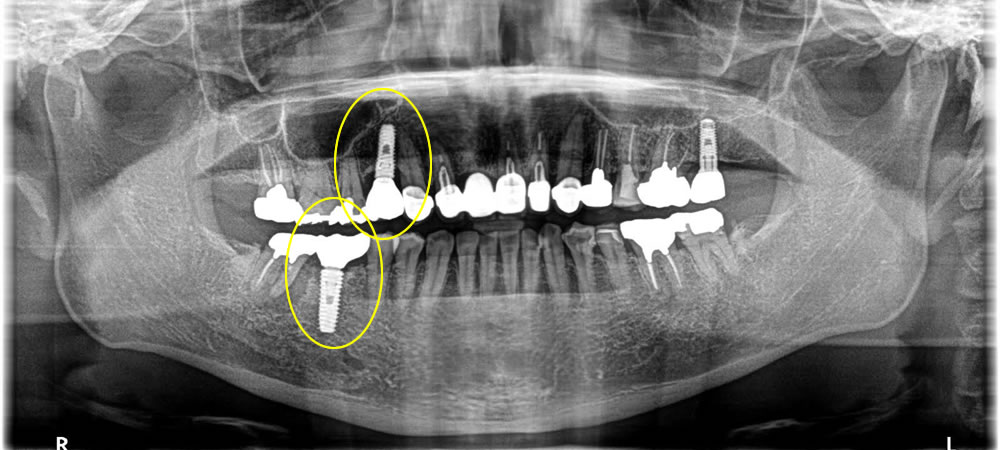

After

| 年齢 | 40代 |

|---|---|

| 性別 | 男性 |

| 費用 | CT検査 0円 インプラント治療 (上部ジルコニア含め) 小臼歯 429,000円 骨造成 88,000円 大臼歯 407,000円 骨造成 110,000円 |

| 治療期間 | 4ヵ月 |

| 治療回数 | 4回 |